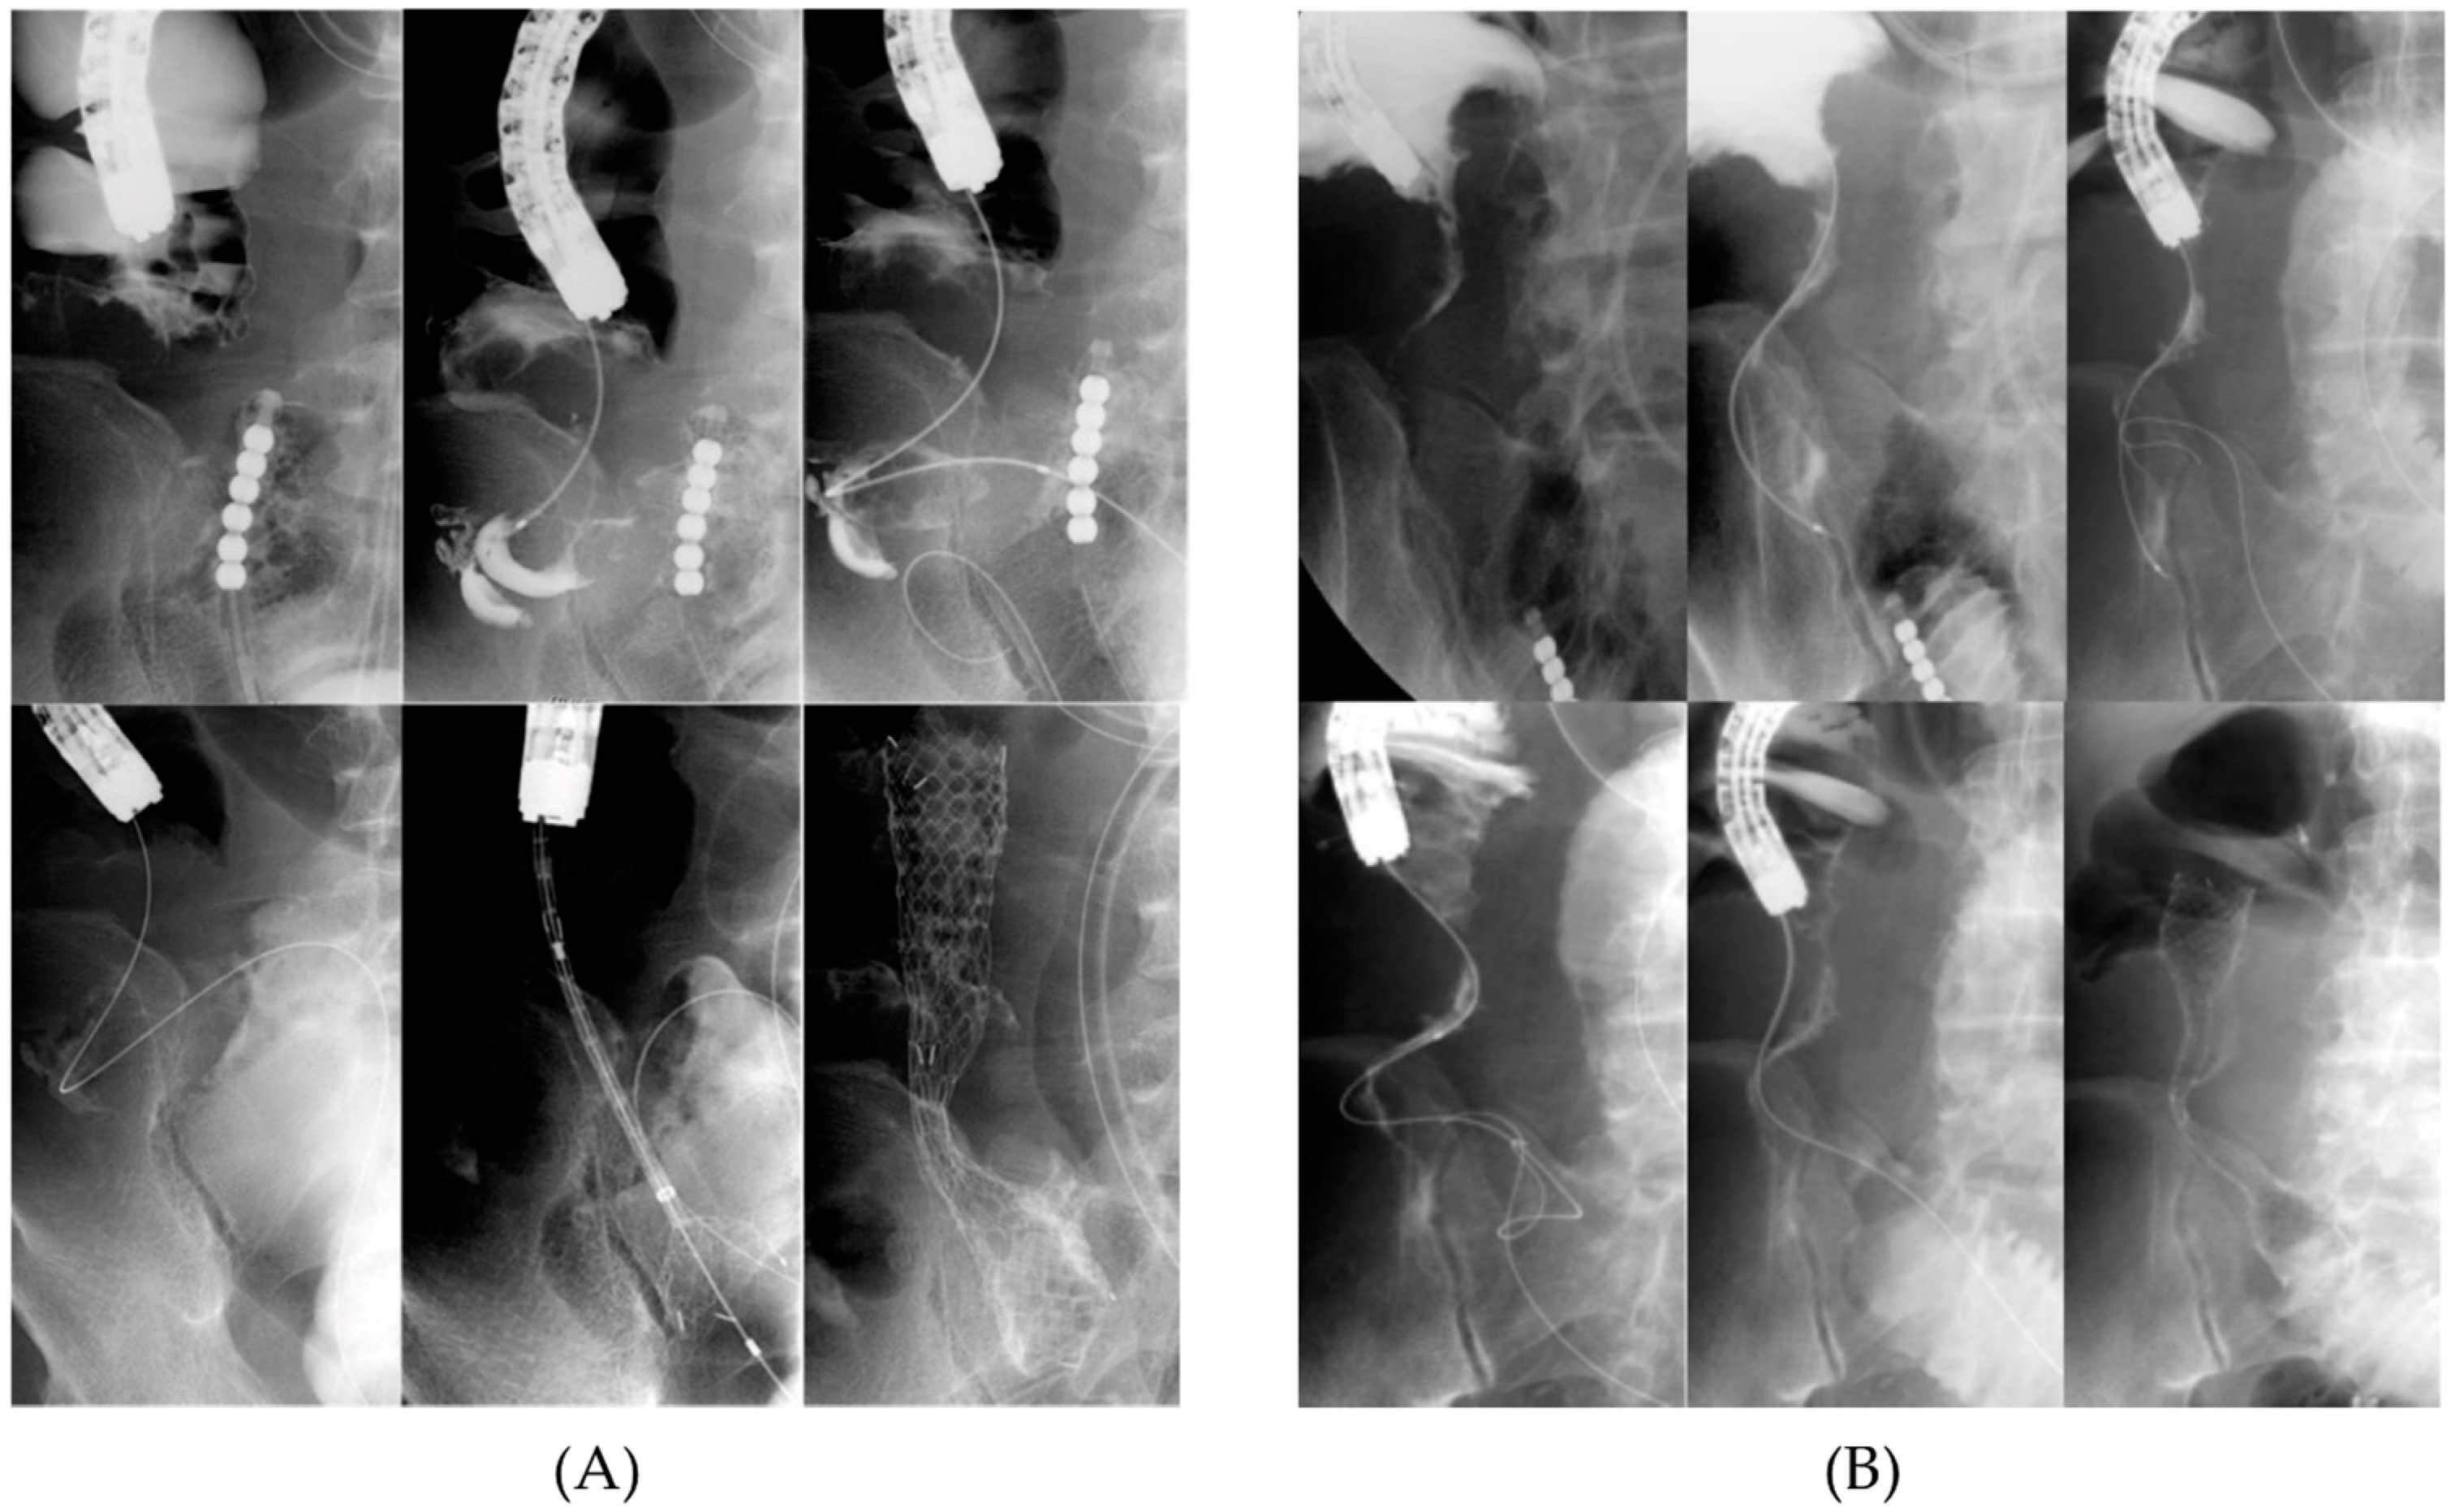

Figure 3. SEMS placement for ileocecal obstruction. (A) A contrast agent was injected through an orally placed long intestinal tube to visualize the conjugation and carefully direct a guidewire with ERCP catheter toward the terminal ileum and (B) when it was impossible to visualize the conjugation, another guidewire was directed toward the colon through an orally placed long intestinal tube. After successfully identifying the junction using the oral guidewire as a landmark, another guidewire from the anal side was directed towards the terminal ileum for SEMS insertion. ERCP, endoscopic retrograde cholangiopancreatography catheter.

To overcome the challenge of ICVO, we used a strategy involving a two-step procedure for colonic stenting, particularly in cases with severe small-intestine dilation. The first step, inserting a long intestinal tube before colonic stenting, decompressed the dilated small intestine and ensured the safety of the endoscopic procedure. The second step was SEMS placement. If the stricture could not be identified endoscopically (Figure 2) and it was difficult to pass the guidewire through the stricture under endoscopic guidance, contrast media injection or antegrade manipulation through the long intestinal tube facilitated the successful stricture passage of the guidewire (Figure 3).